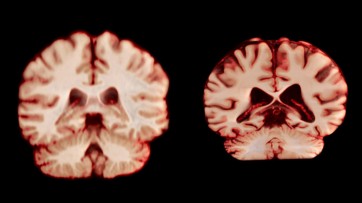

The brain vasculature is important for the developing and mature human brain, and it plays crucial parts in several brain pathologies. Single-cell RNA sequencing enabled the construction of a single-cell atlas of the fetal, adult healthy and adult diseased human brain vasculature, uncovering its molecular architecture and heterogeneity, and capturing reactivated fetal programs as well as conserved properties in the diseased vascular endothelium.